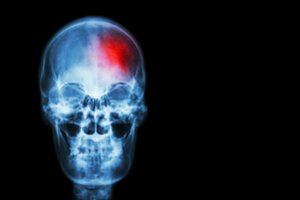

Insultai, kilę dėl aterosklerotinių kaklo arterijų pažeidimų, sudaro 10–35 proc. visų insultų.

„Kaklo arterijų susiaurėjimo ir užakimo sukelti simptomai labai priklauso nuo arterijų pažeidimo lygio, arterijų aprūpinamos krauju smegenų vietos ir nuo smulkesnių kraujagyslių papildomos kraujotakos galimybių“, – pasakojo medikas.

Jei kraujas gali pratekėti kitu keliu, simptomų žmogus kurį laiką gali ir nepajusti. „Dažniausi ligą išduodantys simptomai yra praeinantys smegenų išemijos priepuoliai, nesukeliantys smegenų infarkto. Jie priklauso nuo arterijos pažeidimo vietos“, – aiškino J.Gutauskas.

Dažniausi simptomai, kuriuos jaučia pacientai, – vienos pusės galūnių nusilpimas, regos, kalbos, pusiausvyros ir koordinacijos sutrikimai, taip pat sąmonės ar atminties sutrikimai.